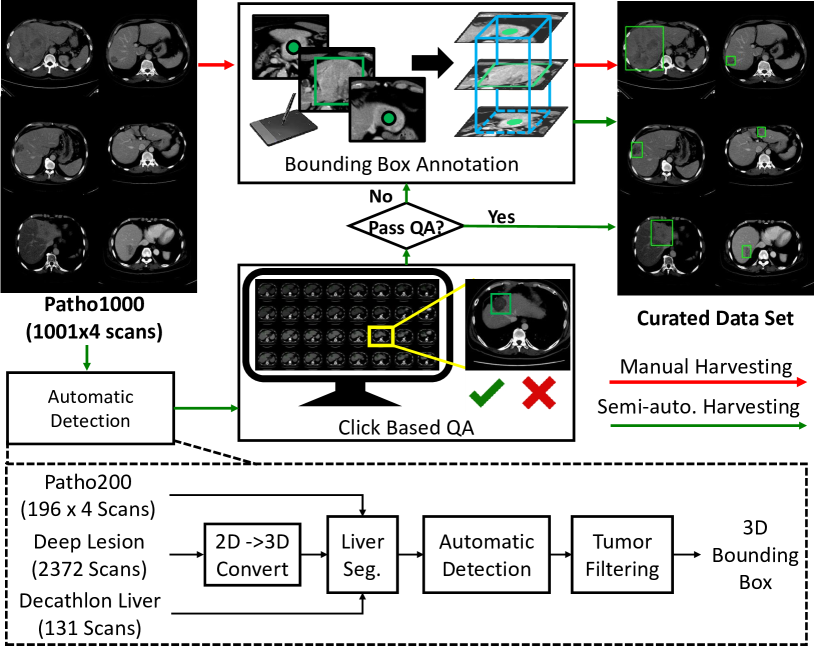

Ideally we would possess as large a dataset as possible of \acCT volumes, all with bounding-box-labeled primary lesions. More typically though, one would only possess a small cohort of fully-labeled patient data, , where and denote the image-level label of lesion type and bounding box or mask labels, respectively. It also typically possible to obtain an even larger cohort of patient data with only image-level labels, e.g. data mined from hospital archives. We denote the weakly labelled data , where . Based on our calculations, annotating 3D liver lesion bounding boxes consumes roughly minutes per \acCT study (Fig. 7) by a board-certified physician, making it prohibitive to completely annotate all patient studies. Therefore we wish to develop scalable weakly supervised learning and data curation methods to deal with any large-scale dataset.

Fig. 4 illustrates our approach. First, we collect or harvest a large collection of CT liver lesions from the public LiTS [23] and DeepLesion [22] datasets. For the latter, we select liver lesions by employing the LesaNet [51] produced semantic tags on identifying the lesion types. Using our own labelled multi-phase CT data, , and the single-phase public CT data [23, 22], we train our 3D CenterNet variant of Sec. II-A. To harmonize the differing channel numbers of single (public) and multi-phase (private) CT data, we simply treat all CT phases as individual/independent observations.

With a tumor detector trained, we apply it to . This provides us with a cohort of lesion candidates, but also a corresponding share of false positives. For each multi-phase CT volume , we obtain the tumor predictions from each phase, project them into the same volumetric space and merge the resulting candidates via non-maximal suppression [27]. We then render each candidate bounding box, along with the corresponding multi-phase \acCT intensities, into a 2D image representation using a grid layout. These 2D images can then be easily categorized into true or false positives using an efficient mouse-click-based \acQA process. This takes on average one minute to verify all tumor candidates per study by a clinician, reducing the annotation labor by at least one order of magnitude. While this filters candidates into true and false positives, it is still possible to encounter studies where none of the detection candidates overlapped with the primary lesion(s) (for diagnosis). For these cases, they have to be mannually annotated from scratch. In our work, these constitute of volumes in , meaning the labor required for annotation has still been considerably reduced. With this data curation pipeline in place, we can effectively and successfully harvest the liver tumor bounding boxes for the large-scale , which significantly benefits both the downstream detection and classification performance. More importantly, our weakly supervised and human-in-the-loop data curation pipeline provides an annotated patient cohort with detected-verified/drawn tumor proposals we can use for the next process of primary tumor selection.

Since only Patho-200 has localizations, we use the data curation pipeline of Sec. II-B to extract tumor \acpROI from Patho-1000. The labor savings () provided by the curation is presented in Fig. 7. In total, this required employing our mouse-click \acQA on lesion candidates ( min/study) and executing 3D bounding box annotations ( min/study) on 193 patients whose primary tumors were not captured by the proposals. Our test set consists of patients ( multi-phase CT scans), which were fully annotated by our collaborating physician with years of experience. This population is comparable or larger than previous studies [12, 11, 10].